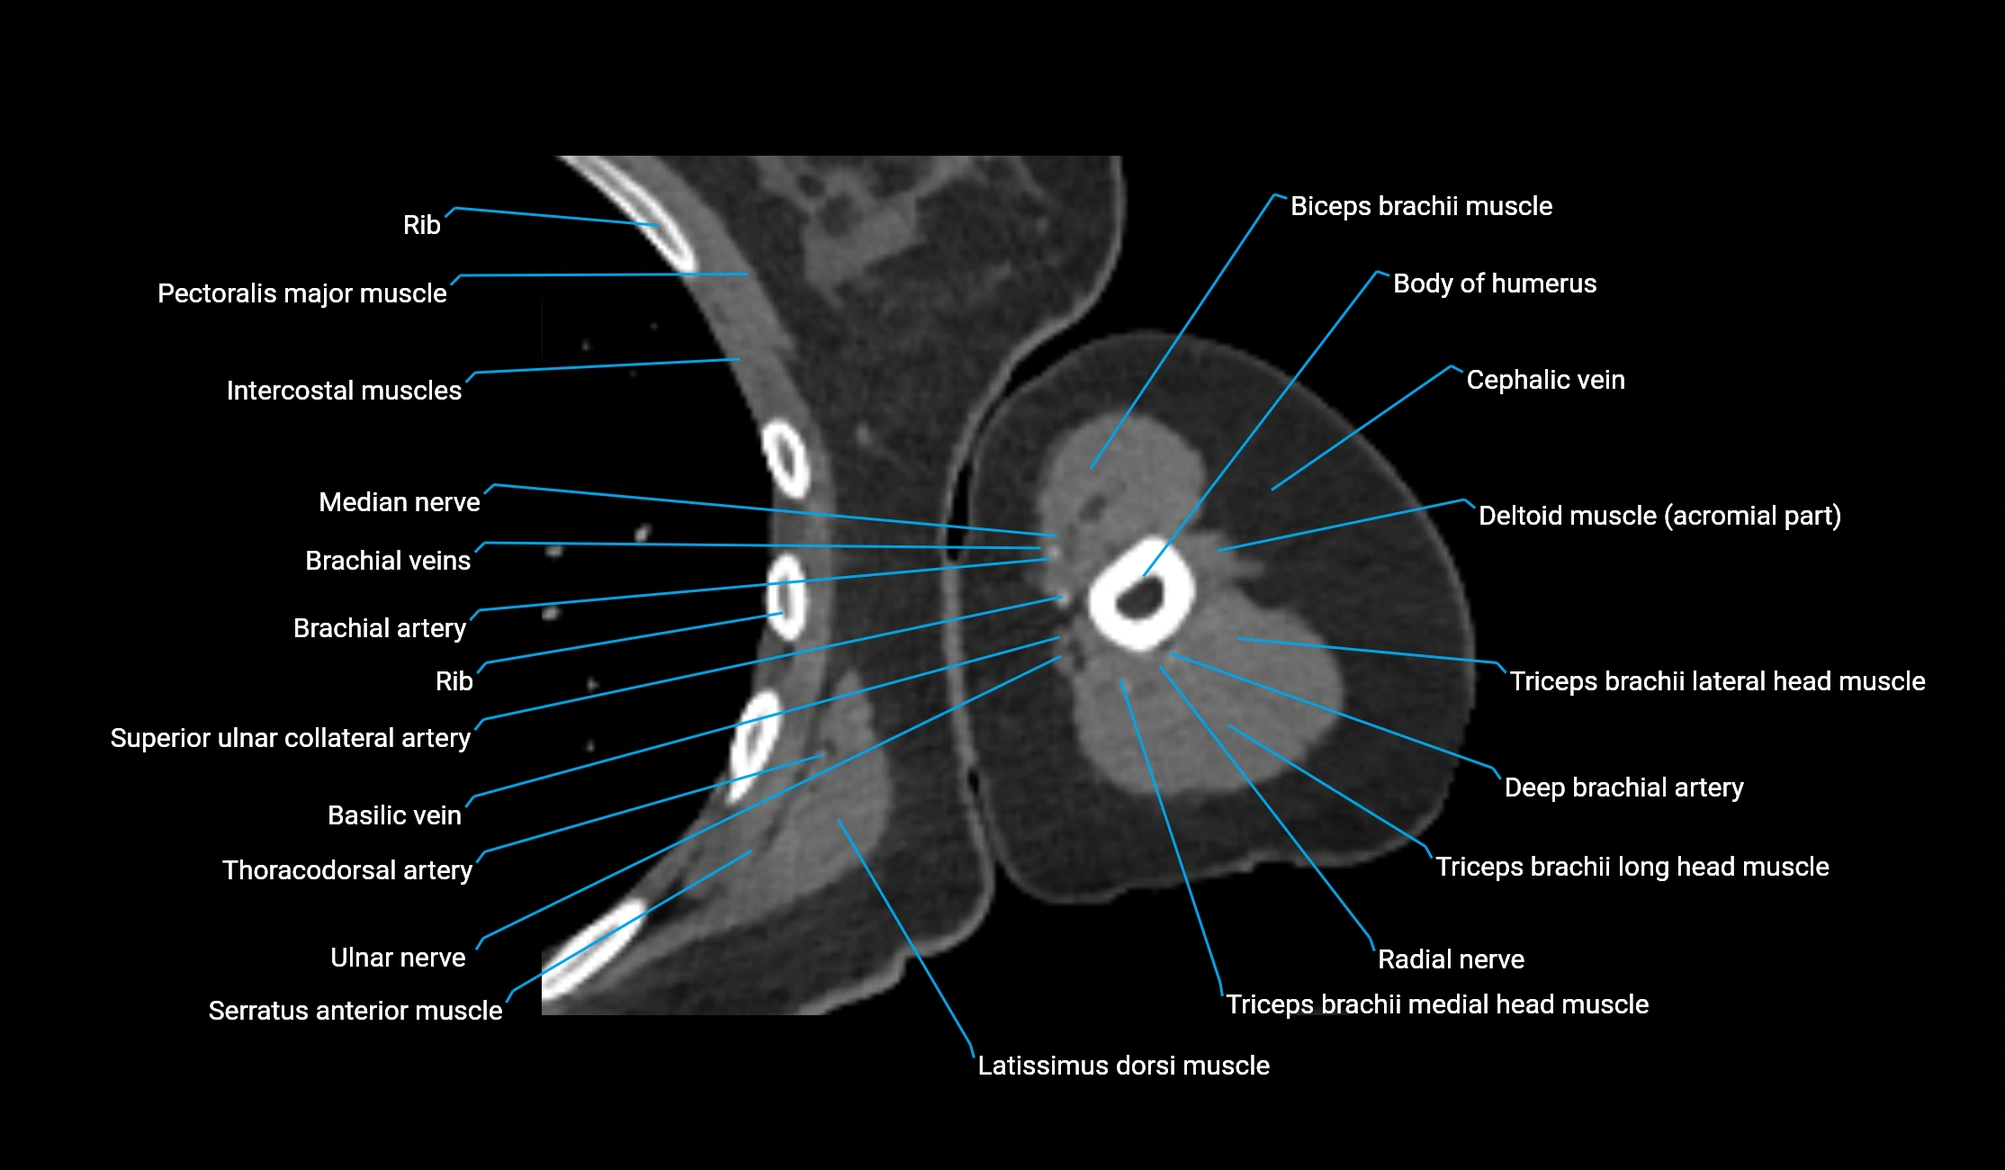

CT Appearance

Non-Contrast CT:

-

Muscle: soft-tissue density, well defined in the hypothenar region.

Tendon: linear low-density structure extending to the base of the little finger.

Calcification or chronic scarring may appear as localized high-density foci.

Useful for assessing bony attachment sites at the pisiform and proximal phalanx.

Post-Contrast CT (standard):

Normal muscle: homogeneous mild enhancement.

Inflamed or injured muscle: increased enhancement and surrounding soft-tissue edema.

CT image